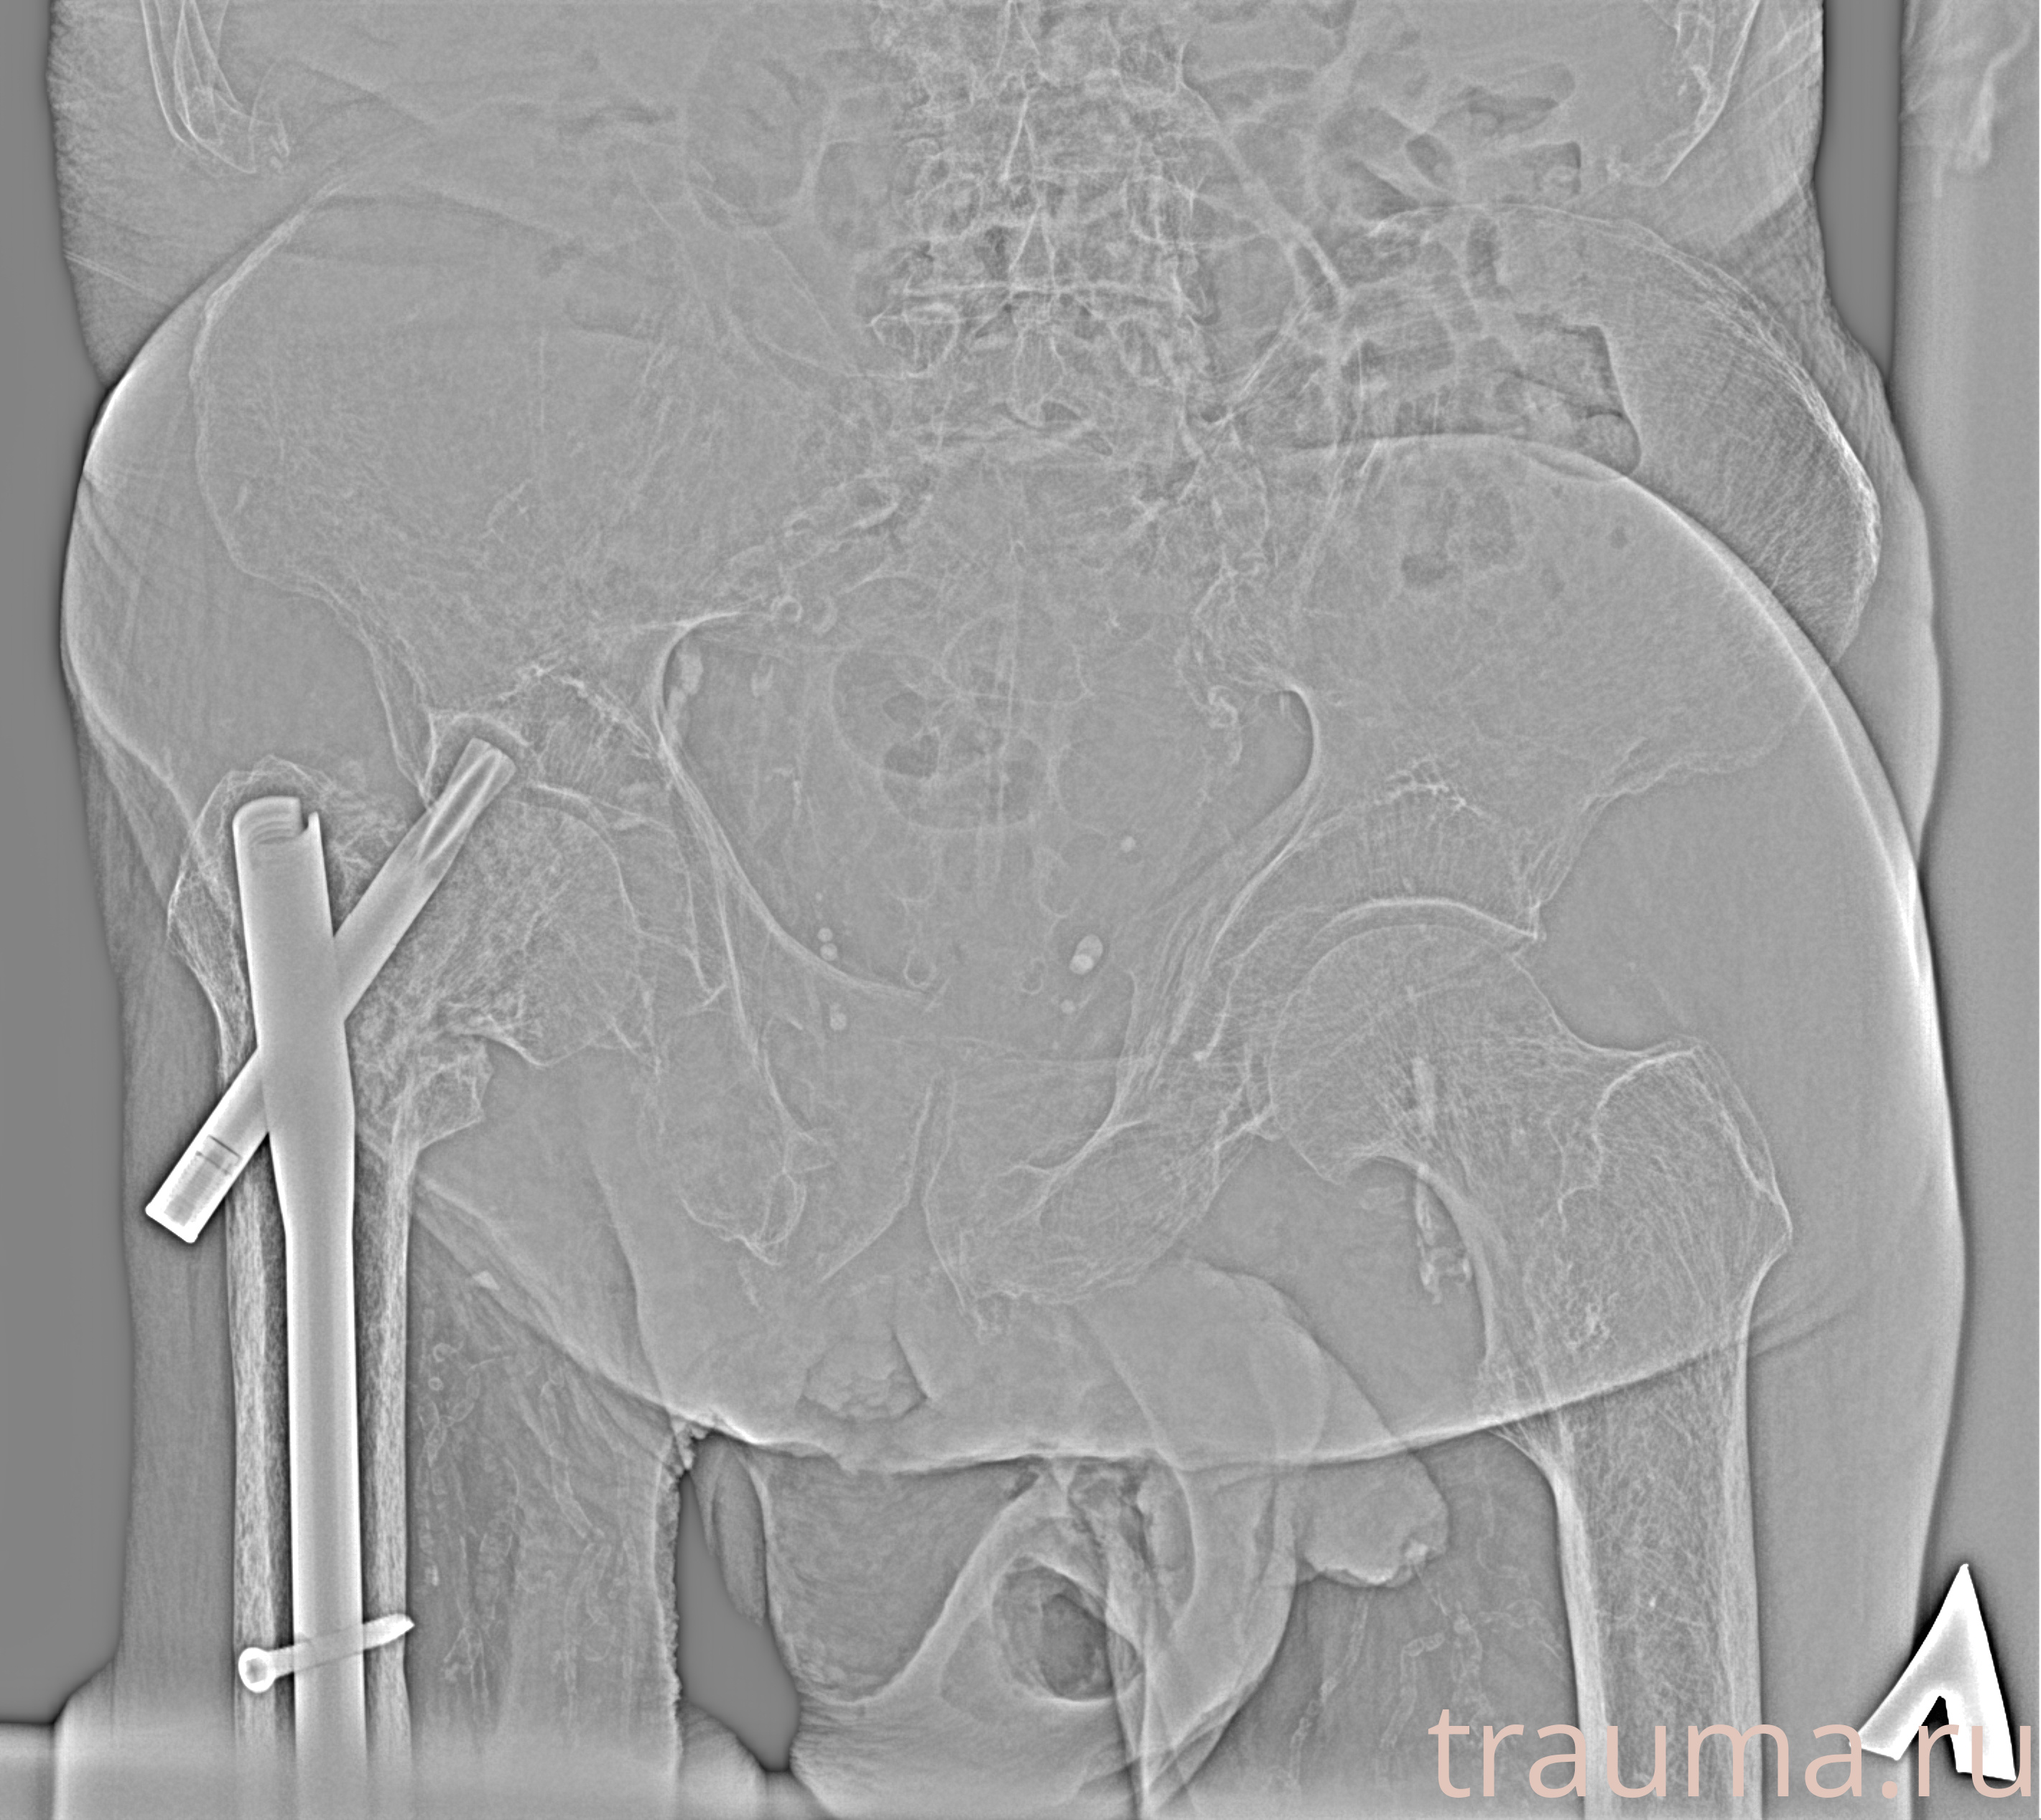

Рентген на дому: по вашему адресу приезжает врач-рентгенолог, травматолог-ортопед с мобильным рентгеновским аппаратом, проводит диагностику травмы или заболевания, делает необходимые рентгенограммы, дает рекомендации по дальнейшему лечению. Получить качественные снимки в домашних условиях возможно благодаря уникальной методике, разработанной МосРентген Центром для института  Склифосовского